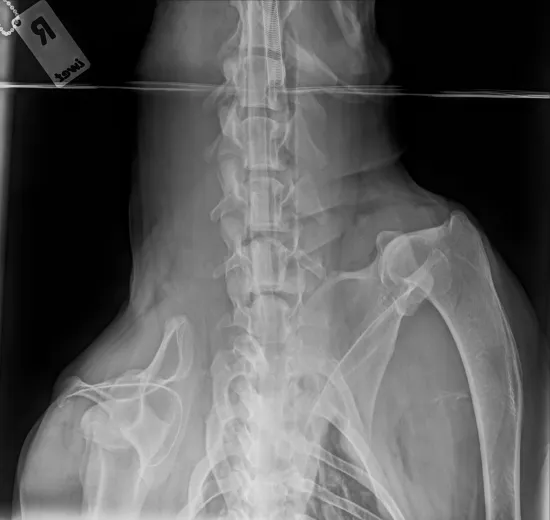

Niedawno trafił do nas starszy pies znaleziony przez pracowników stacji uzdatniania wody. Leżał skulony pod drzewem, cichy, bezbronny, jakby już pogodził się z losem. Kiedy pojechał po niego pracownik schroniska, szybko okazało się, że coś jest bardzo nie tak - pies ledwo się poruszał, z trudem wstawał, każdy krok sprawiał mu ból. Wezwany lekarz weterynarii stwierdził wstępnie zmiany zwyrodnieniowe, podał leki przeciwbólowe i wyraził zgodę na przewiezienie psa do schroniska. Niestety, gdy działanie leków zaczęło ustępować, Magik znów ledwo podnosił się z posłania. Zabraliśmy go do naszego weterynarza na dokładną diagnostykę. Dziś wiemy już więcej. Magik ma około 11 lat, a badania RTG wykazały poważne zmiany w kręgosłupie. Lekarz widzi wskazanie do operacji, ale zanim podejmiemy jakiekolwiek decyzje, konieczne jest specjalistyczne badanie - rezonans, które pokaże, co dokładnie dzieje się z rdzeniem kręgowym i czy operacja ma sens oraz jakie daje rokowania. Takie badanie możemy wykonać tylko w klinice we Wrocławiu. Koszt: 2500 zł. Od tego badania zależy dalszy los Magika. Jeśli okaże się, że można operować - zrobimy wszystko, aby dać mu szansę na życie bez bólu. Na operację uruchomimy osobną zbiórkę.